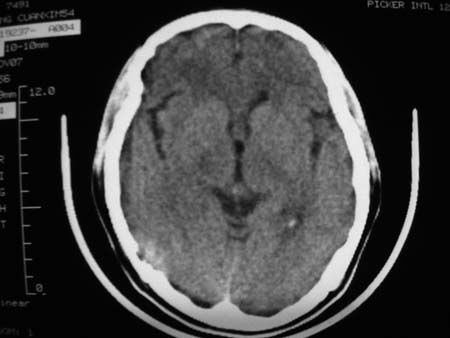

男,54岁,十天前被钢管打伤头顶部,现自述头部不适,视物模糊,并于两天前发觉右枕部有包块,既往未有明显异常.

颅骨多处骨质不完整,内板变薄,右侧额颞部局部呈“穿凿样”骨质缺损,相应区硬膜外密度略增高。多考虑:骨嗜酸性肉芽肿!

颅骨多处骨质不完整,内板变薄,右侧额颞部局部呈“穿凿样”骨质缺损,相应区硬膜外密度略增高。多考虑:骨髓瘤或骨嗜酸性肉芽肿!

骨嗜酸性肉芽肿密度可以这么高么?能不能是脑膜瘤.